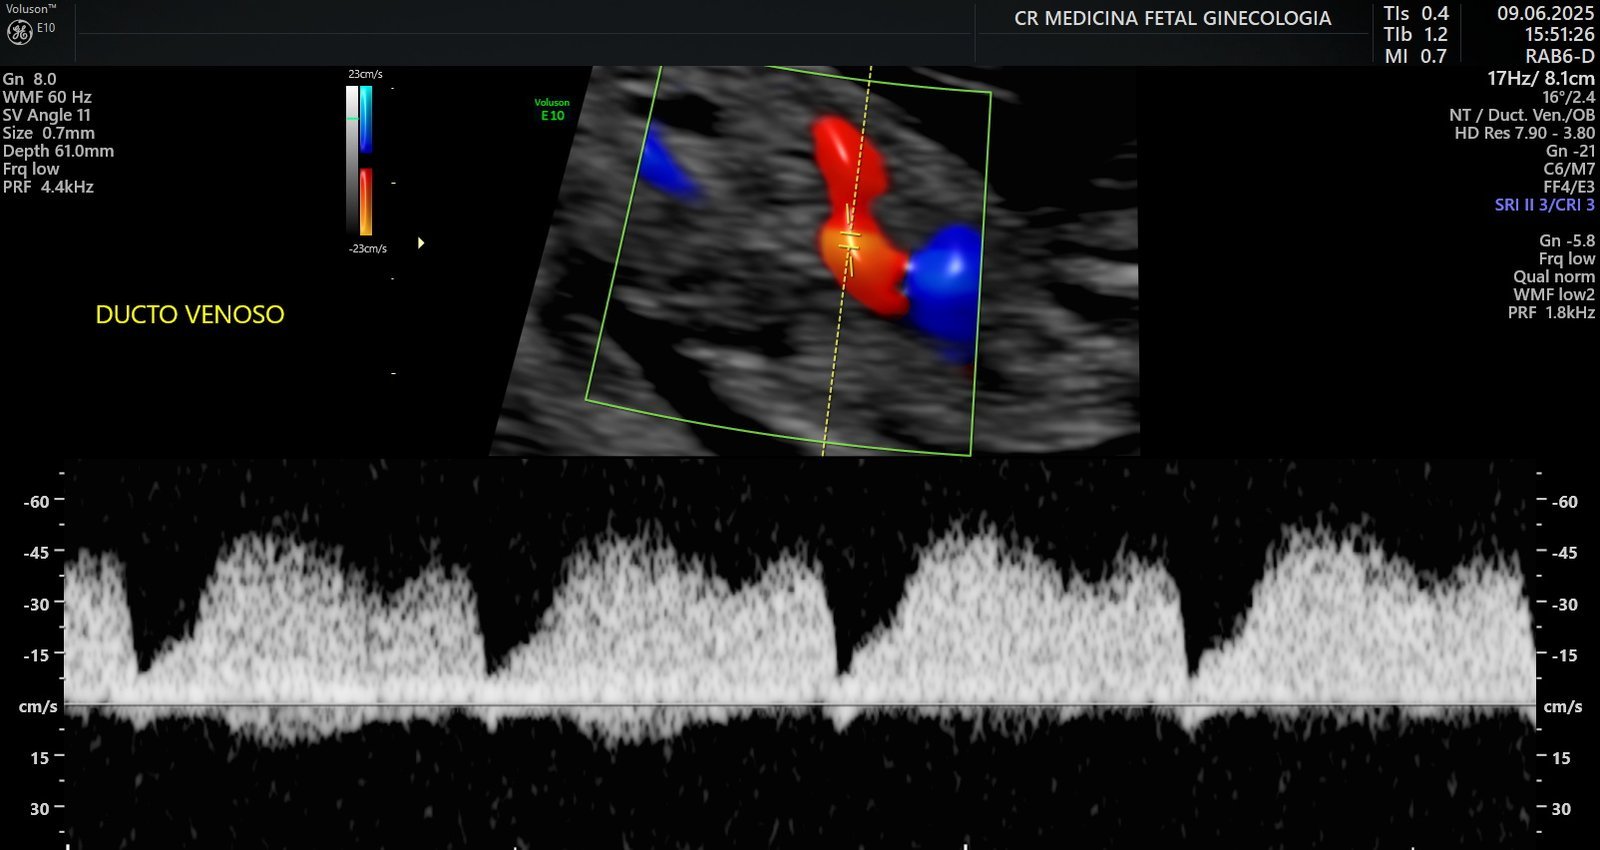

Ultrassonografia obstétrica morfológica do primeiro trimestre: Exame detalhado realizado entre a 11º – 13º semana, avalia a formação inicial do bebê e identifica possíveis riscos genéticos ou malformações precoces e chances maternas de desenvolver pré-eclâmpsia

Ultrassonografia obstétrica morfológica do segundo trimestre: Realizado entre a 20ª e a 24ª semana, analisa minuciosamente a anatomia fetal, incluindo coração, cérebro, rins, membros e outros órgãos vitais, além do cálculo de risco para parto prematuro através da medida de colo e nova avaliação de artérias uterinas com o Doppler.

Avaliações de crescimento e ganho de peso fetal no terceiro trimestre: Monitoramento da curva de crescimento, da nutrição e do bem-estar do bebê, garantindo segurança até a reta final da gestação.